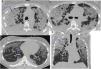

Patient diagnosed with PLCH, smoker of three packs/day. Axial HRCT slices and coronal reconstruction. Images from 2010 (a–c) reveal a greater profusion of cavitated and non-cavitated pulmonary nodules and cysts (blue arrows). In those from 2011 (images d–f), cysts (blue arrows) are observed, some of very variegated morphology, which were complicated by a left pneumothorax (orange arrow). The cysts leave the lung bases, and the costophrenic angles preserved and are less numerous in the anterior areas.

The HRCT findings (Fig. 1a–f) also vary with the evolution of the disease, in parallel with the histological findings. In the initial phases, centrilobular nodules of one to 10mm appear, which cavitate as the disease progresses, finally becoming thin-walled cysts. In the intermediate phases, the characteristic pattern in HRCT is a combination of nodules and cysts with walls of intermediate thickness, generally of irregular morphology, which predominate in the upper and middle lung fields, with the costophrenic recesses and the anterior zones of the lung preserved11,14 In more advanced stages, the predominance of irregular thin-walled cysts that can measure up to 20mm in diameter is typical. Lung volumes are usually preserved or increased. Reticulation, emphysema, and areas of fibrocystic distortion may coexist.17 Ground-glass opacities may also appear, which correlate with the presence of RB and DIP histological changes, supporting the idea that PLCH, RB, and DIP comprise a spectrum of lung injury in smokers.5